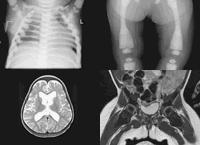

4.X線顱骨平片 顯示顱骨異常緻密及增厚,內外板及板障合為一體,難以分辨。顱骨高度鈣化密度顯著增高,顱窩變淺,垂體窩變小,額竇縮小,鞍背增生等。

石骨症為全身性骨骼受累的疾病,顱骨的X線表現為硬化,尤以顱底為顯著,特別是蝶骨體及大、小翼均明顯改變。蝶鞍大小正常或縮小,床突、鞍底皆硬化。顳骨及枕骨也可硬化,使板障封閉,失去三層的分野。頂骨額骨及顏面骨可不受侵犯或僅有輕微變化。視神經孔變窄且邊緣模糊乳突小房及鼻旁竇變小或發育不全石骨症在長管狀骨及脊椎有特徵性的X線改變。脊椎椎體表現為上下緣特别致密,其間密度低者為正常骨質,組成三層帶狀影。長管狀骨表現為“骨內骨”,骨質緻密髓腔變窄或消失於乾骺部顯示多條互為平行或呈波狀緻密線紋,乾骺部可呈杵狀變形,尤其脛骨上端內側可表現為邊緣不整呈粗鋸齒改變,髂骨翼典型改變為平行髂嵴的多層的同心弧狀硬化帶此外,肋骨和鎖骨均可呈均勻硬化。有時還可見到骨折,於掌、蹠、指及趾骨常有界限分明的骨島出現。

(5)顱骨穹窿顱底均增厚硬化,以顱底骨質增生最明顯。